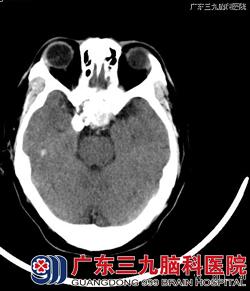

入院行CT及MRI检查:头颅CT平扫:蝶窦腔内及鞍上可见一不甚规则的占位性病变,病变部分边缘及内部可见多发斑片状钙化影,蝶窦窦壁骨质大部分吸收、破坏。MRI检查:鞍区、蝶窦区示一不规则团块状异常长T1短T2信号影,其内示散在斑点状等、稍短T1长T2异常信号影,部分边缘示斑条状T1WI更低信号影,呈不规则环形强化,范围约34.8mm×30.5mm×37.8mm,部分凸向鞍上,推移双侧颈内动脉海绵窦段,垂体显示不清。斜坡部分受压骨质吸收。术前影像诊断:考虑骨源性肿瘤。术后病理:组合型牙瘤。镜下见蝶窦内充满大量灰黄色沙粒样物,质软,血供不丰富,手术予以刮匙镜下全部刮除,可见蝶窦上方及岩斜处骨质破坏,硬脑膜完整,未见脑脊液流出。www.999brain.com

CT骨窗 CT平扫

广东三九脑科医院影像诊断中心汪文胜主任表示,本例特点:1.发生在蝶窦区,国内外未见有报道。病因考虑为牙源性上皮和间叶组织异位到蝶窦区所致。2.发病年龄偏大,但病人病史长达20年,是否为20年前就已经存在该病变,无法证实。3.关于牙瘤的MR或CT影像表现,国内相关文献未见有报道。本例影像特点:钙化特别多,蝶窦窦壁骨质大部分呈吸收改变,破坏相对较少,符合良性病变特点;T2WI以明显低信号为主,增强后,呈不规则环形强化。 www.999brain.com